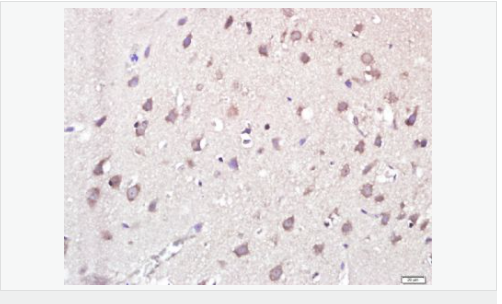

| 产品应用 | WB=1:500-2000 ELISA=1:5000-10000 IHC-P=1:100-500 IHC-F=1:100-500 Flow-Cyt=0.2μg /test IF=1:100-500 (石蜡切片需做抗原修复) not yet tested in other applications. optimal dilutions/concentrations should be determined by the end user. |

| 产品介绍 | This gene encodes a member of the cysteine-aspartic acid protease (caspase) family. Sequential activation of caspases plays a central role in the execution-phase of cell apoptosis. Caspases exist as inactive proenzymes which undergo proteolytic processing at conserved aspartic residues to produce two subunits, large and small, that dimerize to form the active enzyme. This protein can undergo autoproteolytic processing and activation by the apoptosome, a protein complex of cytochrome c and the apoptotic peptidase activating factor 1; this step is thought to be one of the earliest in the caspase activation cascade. This protein is thought to play a central role in apoptosis and to be a tumor suppressor. Alternative splicing results in multiple transcript variants. [provided by RefSeq, May 2013] Function: Involved in the activation cascade of caspases responsible for apoptosis execution. Binding of caspase-9 to Apaf-1 leads to activation of the protease which then cleaves and activates caspase-3. Proteolytically cleaves poly(ADP-ribose) polymerase (PARP). Isoform 2 lacks activity is an dominant-negative inhibitor of caspase-9. Subunit: Heterotetramer that consists of two anti-parallel arranged heterodimers, each one formed by a 35 kDa (p35) and a 10 kDa (p10) subunit. Caspase-9 and APAF1 bind to each other via their respective NH2-terminal CED-3 homologous domains in the presence of cytochrome C and ATP. Interacts with the inhibitors BIRC2, BIRC4, BIRC5 and BIRC7. Interacts (inactive form) with EFHD2. Interacts with HAX1. Tissue Specificity: Ubiquitous, with highest expression in the heart, moderate expression in liver, skeletal muscle, and pancreas. Low levels in all other tissues. Within the heart, specifically expressed in myocytes. Post-translational modifications: Cleavages at Asp-315 by granzyme B and at Asp-330 by caspase-3 generate the two active subunits. Caspase-8 and -10 can also be involved in these processing events. Phosphorylated at Thr-125 by MAPK1/ERK2. Phosphorylation at Thr-125 is sufficient to block caspase-9 processing and subsequent caspase-3 activation. Similarity: Belongs to the peptidase C14A family. Contains 1 CARD domain. SWISS: P55211 Gene ID: 842 Database links: Entrez Gene: 842 Human Entrez Gene: 12371 Mouse Omim: 602234 Human SwissProt: P55211 Human SwissProt: Q4FJK5 Mouse Unigene: 329502 Human Unigene: 88829 Mouse Unigene: 32199 Rat Important Note: This product as supplied is intended for research use only, not for use in human, therapeutic or diagnostic applications. Caspase-9半胱氨酸蛋白酶家族成员之一,又称ICE-Lap6(ICE Like apoptotease 6)参与细胞凋亡过程和细胞因子的加工过程,在许多胚胎和成人组织中都有分布。此抗体主要用于肿瘤凋亡的研究。 |